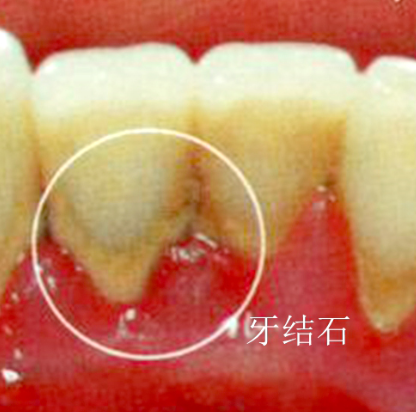

牙結石是牙齒表面鈣化形成的硬質沉積物,主要由細菌、食物殘渣和唾液中的礦物質組成。牙結石一旦形成,僅靠刷牙無法去除,需要通過專業的潔治手段來清除。